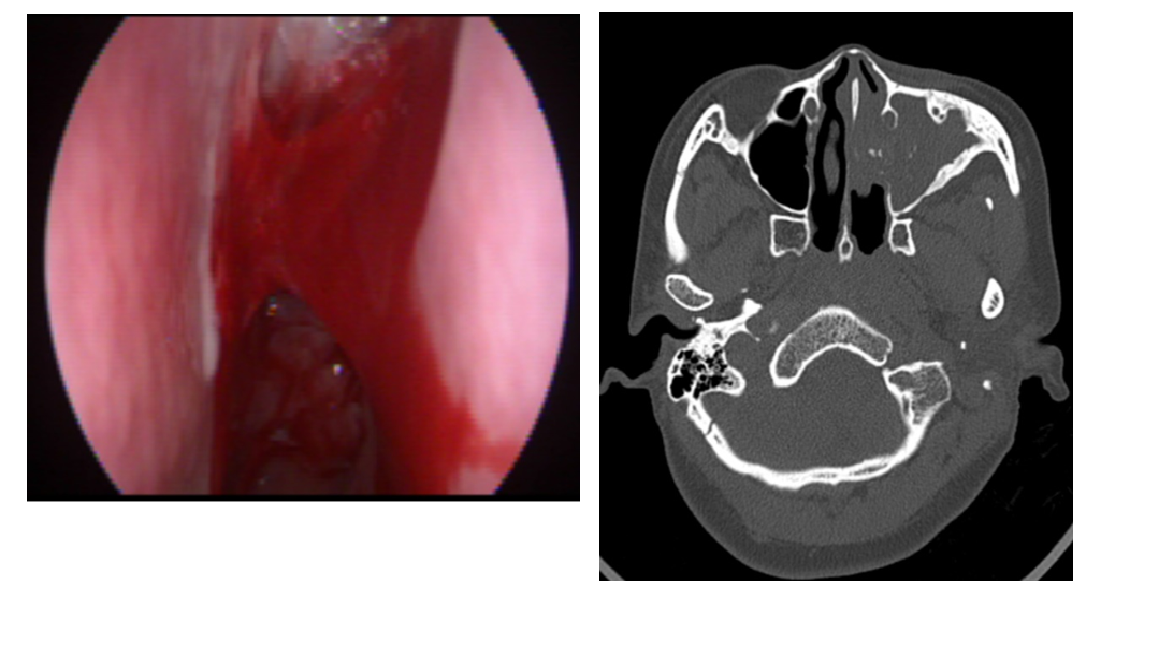

Hình 2: Hình ảnh nội soi mũi tình trạng viêm mũi và sung huyết, phù nề điểm mạch Kisselbach (Little’s area) |

Hình 3: U xơ mạch vòm mũi họng (Juvenile Nasopharyngeal Angiofibroma – JNA) gây chảy máu ở trẻ nam vị thành niên

Hình 5: Bệnh nhân N.T.H 49 tuổi, vào viện vì tình trạng nhức đầu, nghẹt mũi, hơi thở hôi, chảy máu mũi Trái thường tái phát. Phát hiện sớm và nhập viện với chẩn đoán viêm xoang hàm do nấm, được chỉ định phẫu thuật nội soi lấy nấm để điều trị nguyên nhân tại Khoa Tai mũi họng Bệnh viện Quốc tế Becamex, tránh biến chứng ổ mắt, sọ não.

Hình 6: Kết quả sau phẫu thuật bệnh nhân N.T.H 49 tuổi, chảy máu cam nguyên nhân Viêm xoang do nấm Aspergillus.